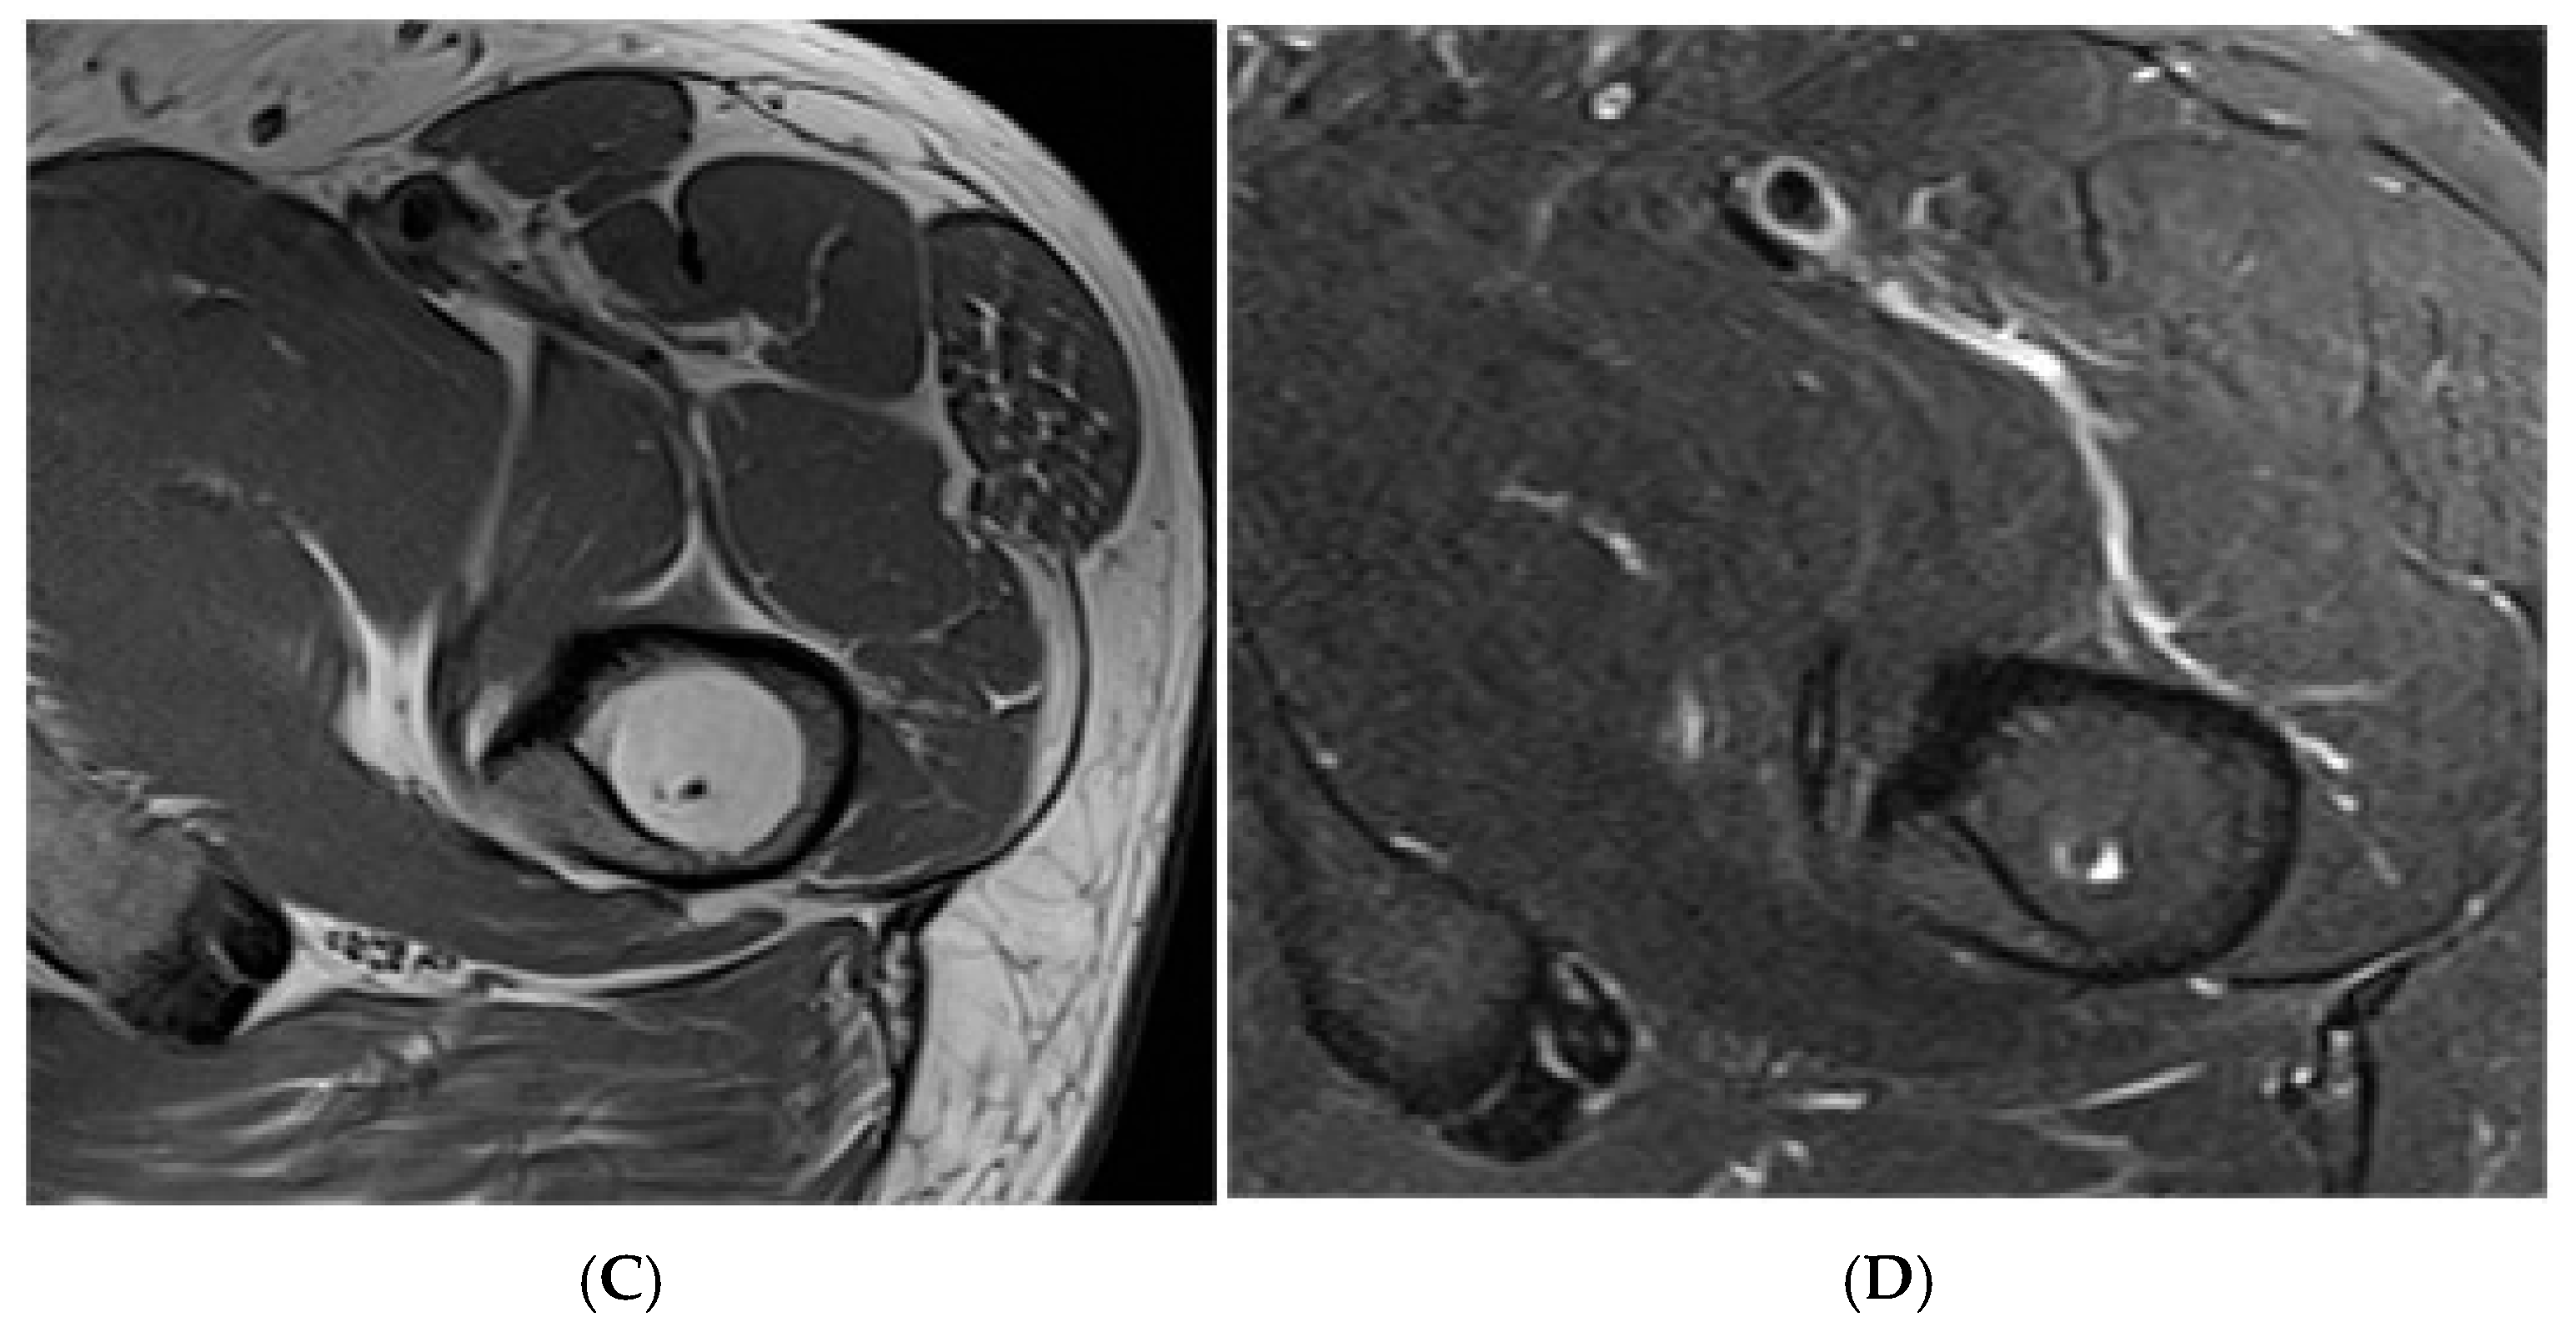

Figure 9.

Bone infarct knee. Coronal T1W and STIR knee MRI demonstrating serpiginous, peripheral low signal intensity with central fat intensity signal (high T1 and low STIR).